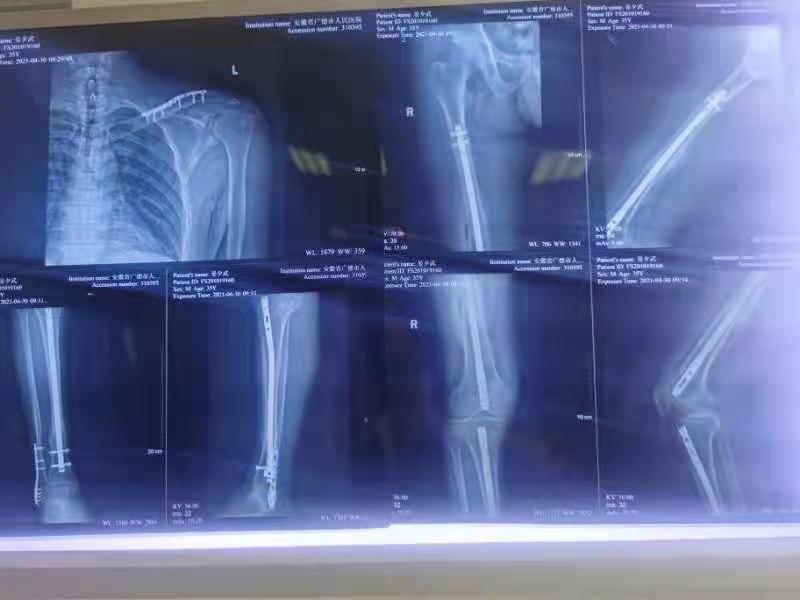

让我们把时钟拨回到2020年4月29日凌晨5时09分,我院急诊接收一名外院转诊的高速车祸患者,经查:颅骨骨折、肋骨骨折、脾破裂、右股骨颈骨折、失血性休克,无家属!医院紧急启动应急机制,急诊完成胸外、普外、心内科、脑外、骨科、重症、超声多学科会诊,总值班授权后紧急行脾破裂切除手术。术中见出血约2200ml,予脾切除、术中自体血回输抗休克等救治。07:06术毕,转入重症医学科继续救治。入住重症期间患者病情极不稳定,先后出现凝血功能障碍、脓毒血症、右下肢室筋膜综合征、肺部感染,紧急请骨科龙术民主任会诊,即予拔除右下肢趾甲,以肝素钠外滴、下肢皮肤开窗减压。损伤控制治疗后进一步检查发现:颅面骨骨折、右胫腓骨骨折、胸骨体骨折、左锁骨骨折、左侧多发肋骨骨折伴液气胸、2、3颈椎椎板骨折。

全院多学科联合救治,进一步细化治疗方案,预防各类并发症,多次和死神较量后,患者的病情终于慢慢稳定。5月7日,在充分评估后行骨科手术。5月8日拔除气管插管。5月11日患者病情稳定,转回当地医院继续治疗。